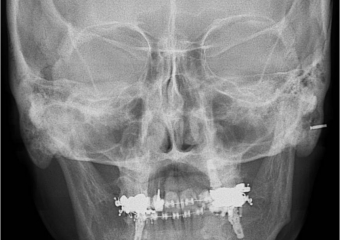

Telerradiografia frontal após a cirurgia